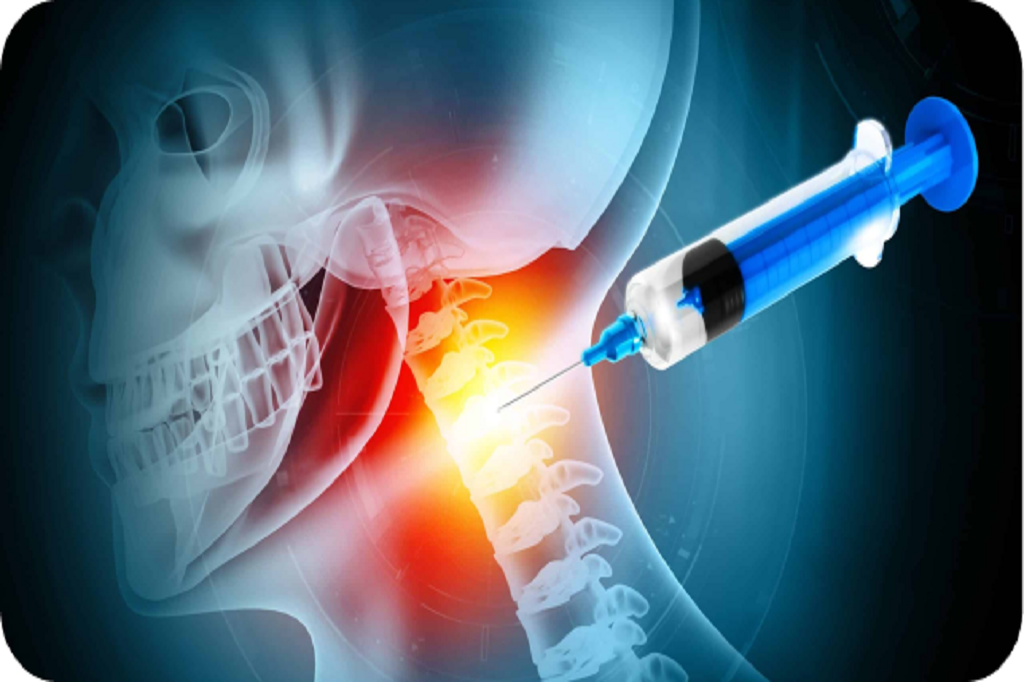

Neck pain is a common condition that can result from muscle strain, poor posture, arthritis, or compression of the nerves in the cervical spine. It may cause stiffness, headaches, or radiating pain into the shoulders and arms. For some, it becomes a chronic issue that affects work, sleep, and quality of life.

Passive treatments like rest or basic painkillers may only offer temporary relief. If pain persists, it’s often because the underlying cause—like nerve irritation or joint inflammation—hasn’t been resolved. This is when targeted, advanced care may be required.

Reduces inflammation around irritated nerves, primarily used to treat radiating pain (radiculopathy) that travels into the shoulders or arms.